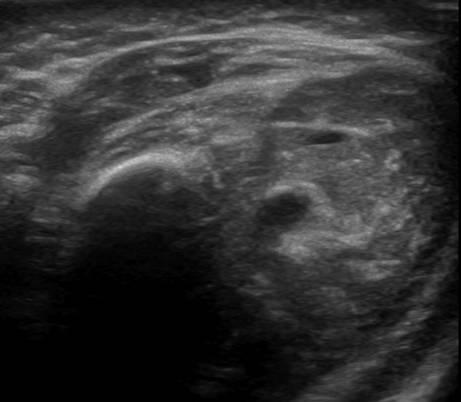

U xơ cơ

» Thông tin: Nữ giới – 3 tháng tuổi.

» Lâm sàng: Sưng vùng đùi.